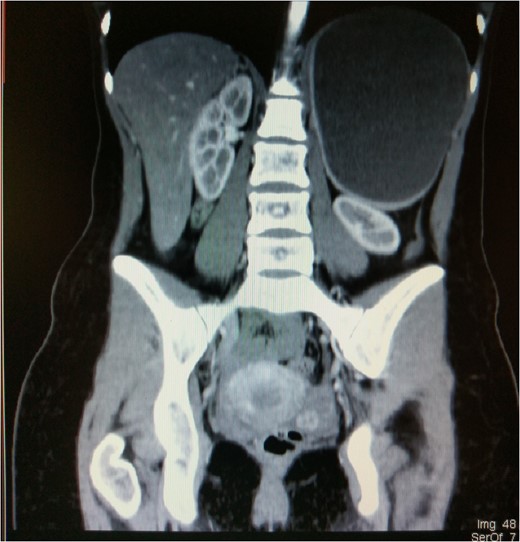

A 23-year-old female presented to the outpatient clinic of our hospital with complaints of abdominal fullness, early satiety, intermittent left upper quadrant abdominal pain and left flank pain for the last 3 months. No significant family history or history of trauma was described. Examination of the abdomen showed a non-tender enlarged mass in the left hypochondrium spanning upto the right iliac fossa. The report indicated a large space occupying lesion in the left upper quadrant of abdomen with probable origin being the spleen. A CT scan of abdomen and pelvis with IV contrast was advised for further evaluation which confirmed a 16.7 × 14.2 × 12.4 cm3 large splenic cyst on the upper outer pole with no intrinsic enhancement or internal septa, having a mass effect on the left kidney pushing it downwards and rotating it while putting a stretch on the left renal vessels (Figs 1 and 2). There was also a mass effect on the body and fundus of the stomach which explains the fullness and satiety by the patient. Serologic testing for Echinococcus was also performed and found to be negative.